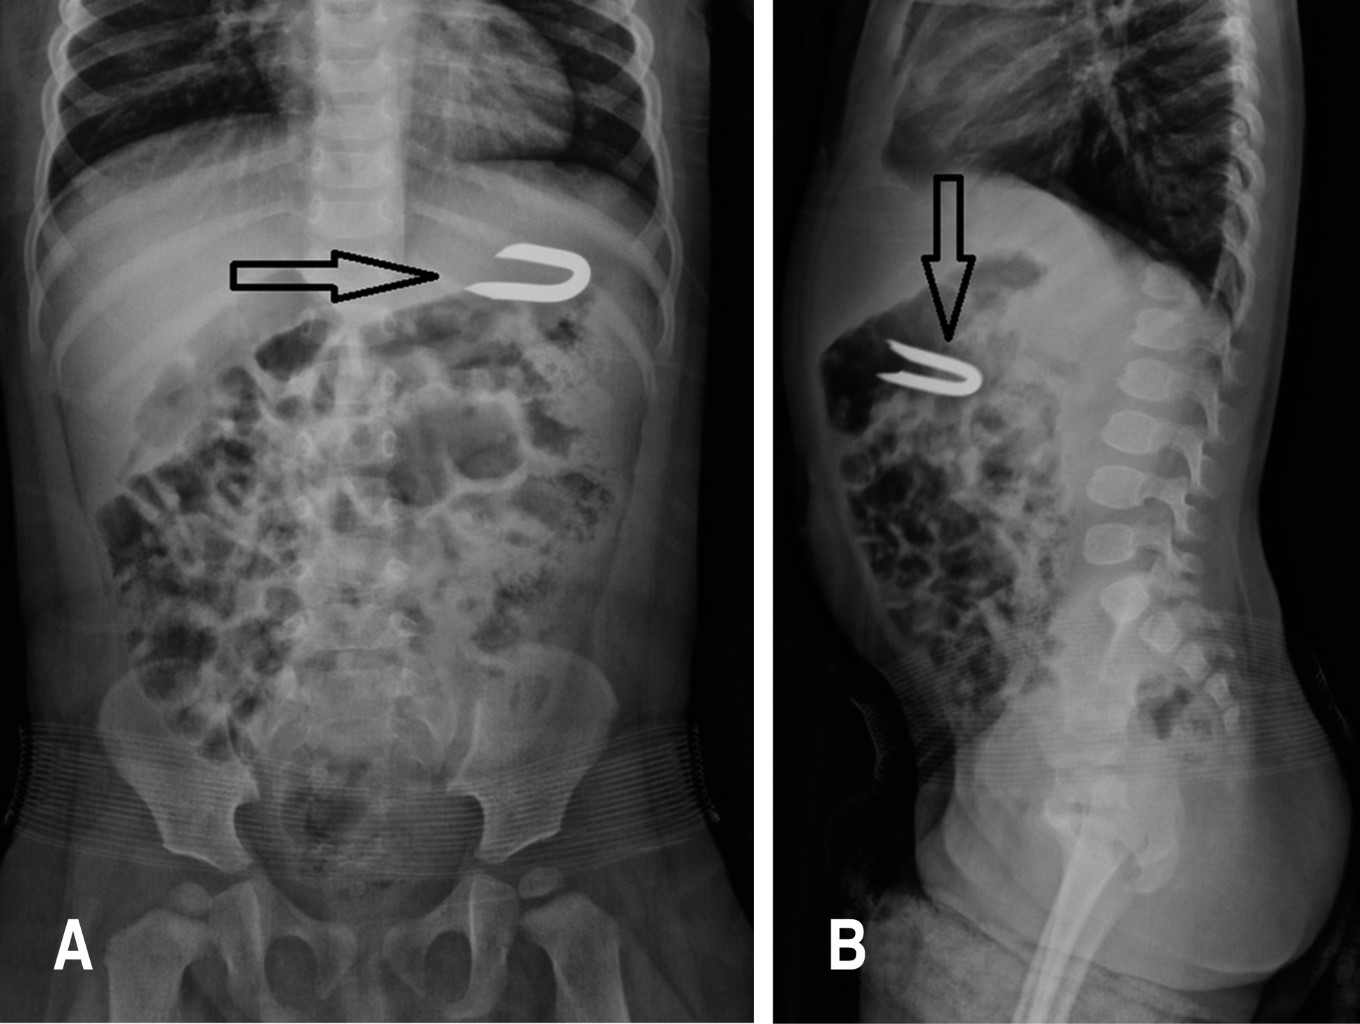

Niña de 14 meses, con historia de tres días de haber ingerido de manera accidental una grapa de acero en forma de U, con puntas biseladas y opuestas, de un tamaño aproximado de 0.9 cm de diámetro por 2.54 cm de largo, la cual se utiliza para fijar el alambre de púas a la madera, cuando se construyen cercas perimetrales.

En la serie radiológica se aprecia el cuerpo extraño ubicado en el hipocrondrio izquierdo (Figura 1). Se realizó endoscopía del tracto digestivo unas horas después de su detección, observando que el cuerpo extraño estaba alojado en la región prepilórica del estómago extrayéndolo con una pinza, sin complicaciones.

Figura 1